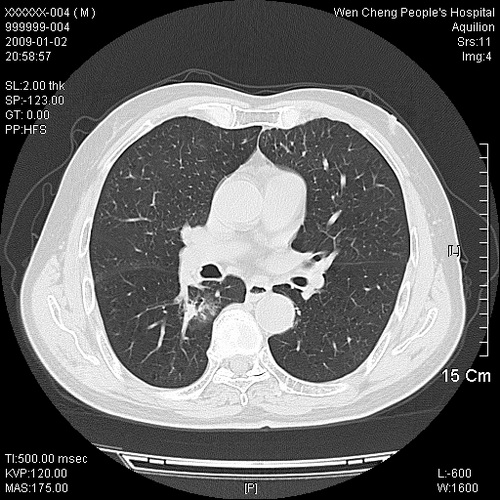

男性,73岁,有慢支病史,肿瘤系列标志物检验正常,血沉及血常规正常

右肺下叶背段小片状 磨玻璃样模糊影,内见血管及含气支气管像,支气管管壁增厚。考虑:慢性炎症!

右肺下叶背段小片状 实性与磨玻璃样影,内见血管及含气支气管像,支气管管壁增厚,边缘见长毛刺影。考虑:慢性炎症或肿瘤!建议抗炎治疗复查,密切观察随访!

右肺下叶片团状影内见扩张的含气支气管和支气管管壁增厚,其周有磨玻璃样模糊影和长毛刺。考虑慢性炎症可能性大。

高度提示细支气管肺泡癌,建议抗炎治疗半月观察病灶变化,如无明显改变,建议立即手术治疗.

病变形态非常不好呀,临床上血常规及症状也不明显,不太支持炎性病灶,高度警惕肿瘤病变,最好做个纤支镜检查。